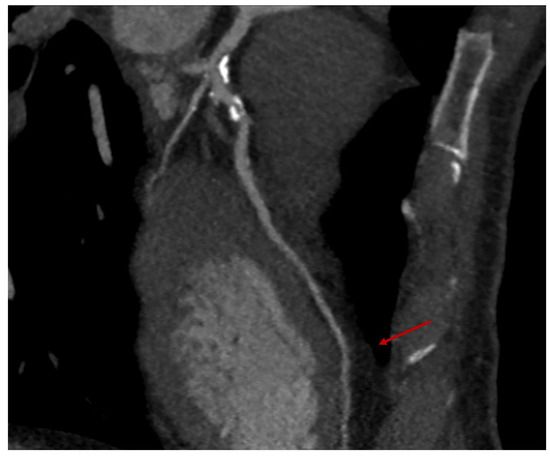

- The risk of an intramyocardial course of the LAD and the consequent possible implication of a sternotomy conversion.